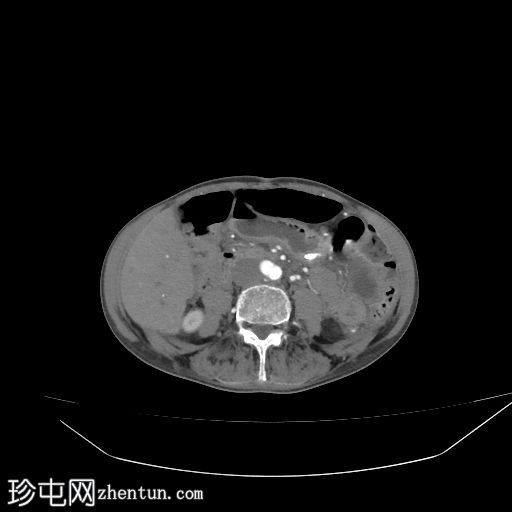

2.jpg

轴位增强扫描

动脉期

盲肠内壁可见多条明显的血管通道,并可见局灶性强化。

动脉期可见一条早期充盈的静脉。静脉期可更清晰地显示扩张的引流静脉。未见活动性出血。